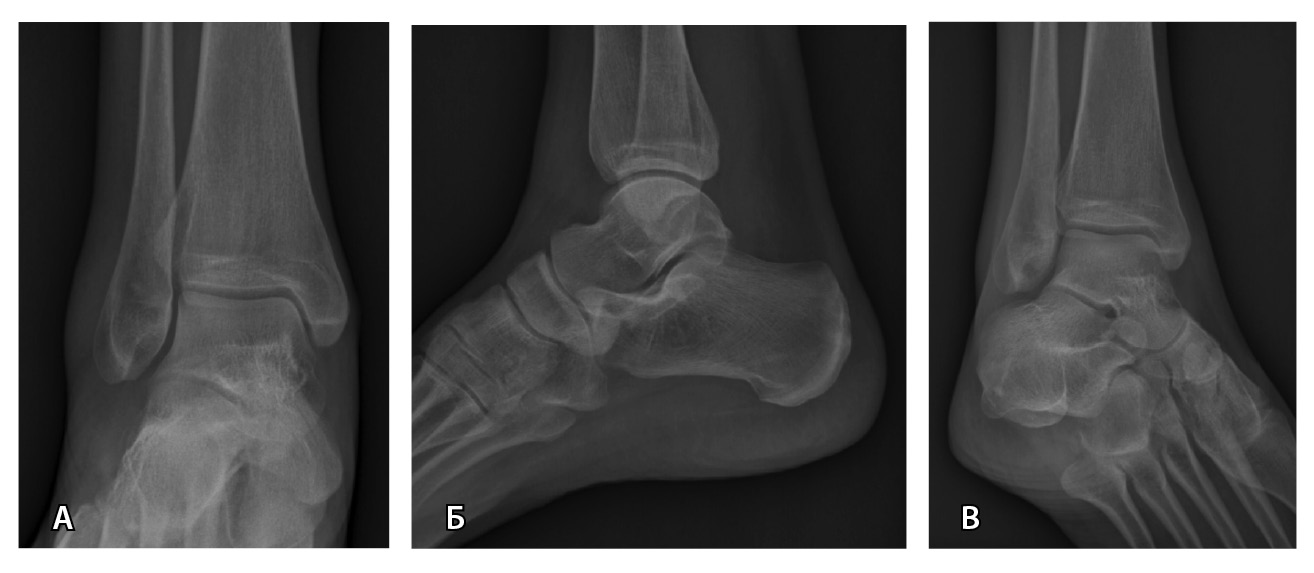

Стандартизированный подход к визуализации помогает снизить количество диагностических ошибок [34]. Стандартный протокол рентгенографии голеностопного сустава представлен в табл. 1 и на рис. 1.

Рис. 1. Стандартный протокол рентгенографии голеностопного сустава без осевой нагрузки: А – прямая проекция; Б – боковая проекция; В – прямая проекция с внутренней ротацией стопы на 20°. Костно-травматические изменения не определяются, параартикулярные мягкие ткани не изменены